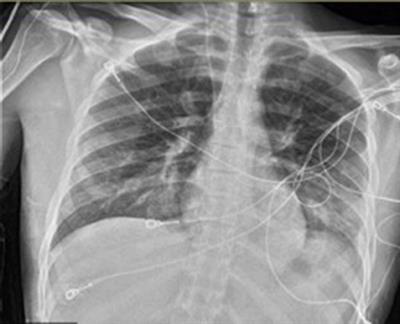

Acute pulmonary oedema is a very frightening experience for the patient and represents a genuine medical emergency. This fluid makes it difficult for the lungs to function (to exchange oxygen and carbon dioxide with cells in the bloodstream). Learn what distinguishes pulmonary edema from pneumonia. A useful tool to differentiate acute cardiogenic pulmonary edema from acute respiratory distress syndrome.